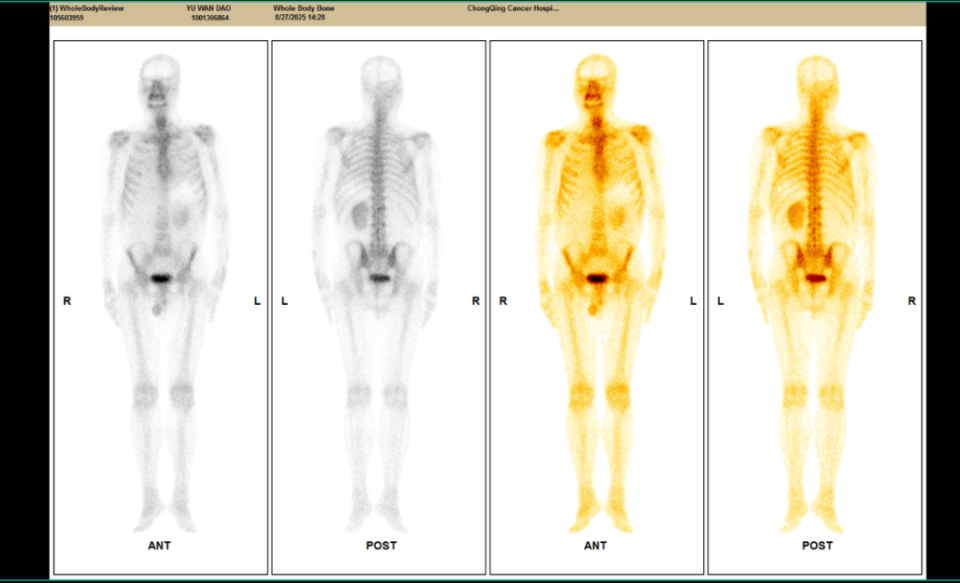

△2023年2月患者基线时CT(左)与2024年4月时CT(右)检查所见对比

△2025年8月疗效评估时患者CT检查(右)较基线(左)对比

△2025年8月疗效评估时患者CT检查(上)及SPECT骨扫描(下)提示新发胸椎转移